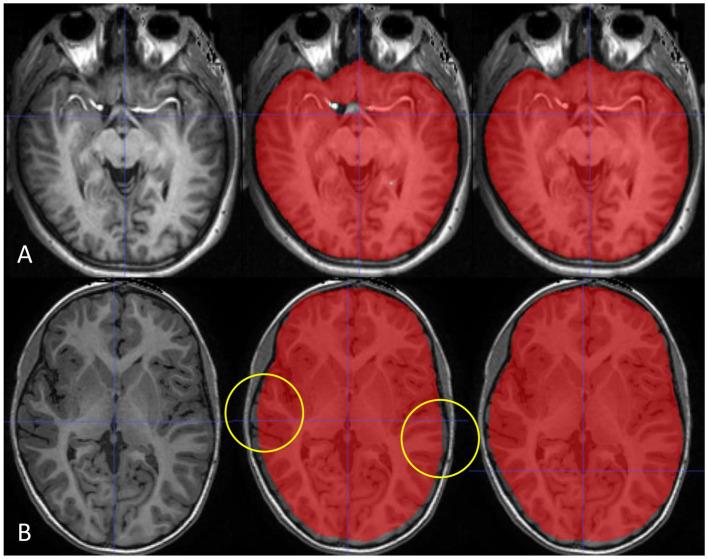

This retrospective study included 60 subjects [30 Alzheimer's disease (AD), 21 mild cognitive impairment (MCI), 9 cognitively normal (CN)] from a single tertiary hospital for the training and validation group (50:10). The test group included 40 subjects (20 AD, 10 MCI, 10 CN) from the ADNI dataset. We propose a robust ICV segmentation model based on the foundational 2D UNet architecture trained with four types of input images (both single and multimodality using scaled or unscaled T1-weighted and T2-FLAIR MR images). To compare with our model, NQ, FS, and SynthSeg were also utilized in the test group. We evaluated the model performance by measuring the Dice similarity coefficient (DSC) and average volume difference.

The single-modality model trained with scaled T1-weighted images showed excellent performance with a DSC of 0.989 ± 0.002 and an average volume difference of 0.46% ± 0.38%. Our multimodality model trained with both unscaled T1-weighted and T2-FLAIR images showed similar performance with a DSC of 0.988 ± 0.002 and an average volume difference of 0.47% ± 0.35%. The overall average volume difference with our model showed relatively higher accuracy than NQ (2.15% ± 1.72%), FS (3.69% ± 2.93%), and SynthSeg (1.88% ± 1.18%). Furthermore, our model outperformed the three others in each subgroup of patients with AD, MCI, and CN subjects.